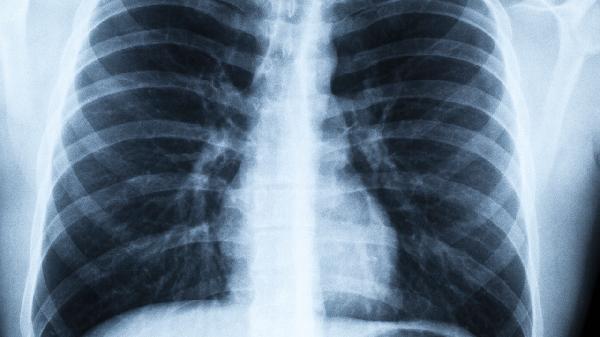

提醒:肺癌早期不是咳嗽,而是身上出现这5大异常,你一定要注意

咳嗽老不好就怀疑是肺癌?其实身体早就给过你更早的预警信号。那些容易被忽略的细微变化,可能才是肺部发出的第一封"求助信"。

这些看似不相关的身体变化,其实是内脏发出的摩尔斯密码。建议35岁以上人群每年做一次低剂量CT筛查,有吸烟史或家族史者可将筛查年龄提前。记住,早期发现的肺癌治愈.率能达80%以上,身体给的提示千万别已读不回。